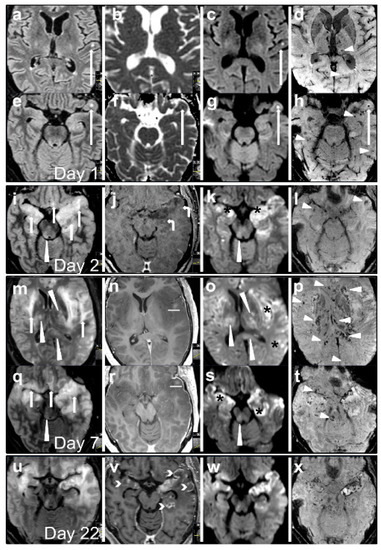

2. Case Description